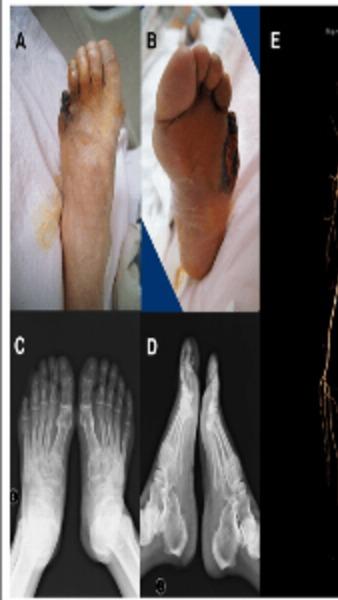

View DetailsWe Provide Best Doctor For Diabetic Foot Problem

View DetailsWe Provide Best Orthopedic Hospital in Nagpur